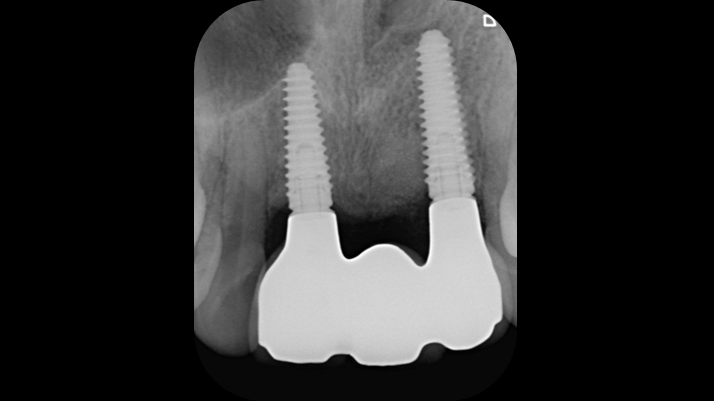

Clinical case: BPET PREDICTABILITY - State-of-the-Art SOCKET SHIELD

- Courtesy of Dr. Howard Gluckman, South Africa -

“AnyRidge is perfect for the anterior esthetic zone due to its strong initial stability & fast osseointegration.

Plus, KnifeThread® ensures space maintenance when using the PET/Socket Shield/Root Membrane Technique, showing excellent bone growth.”